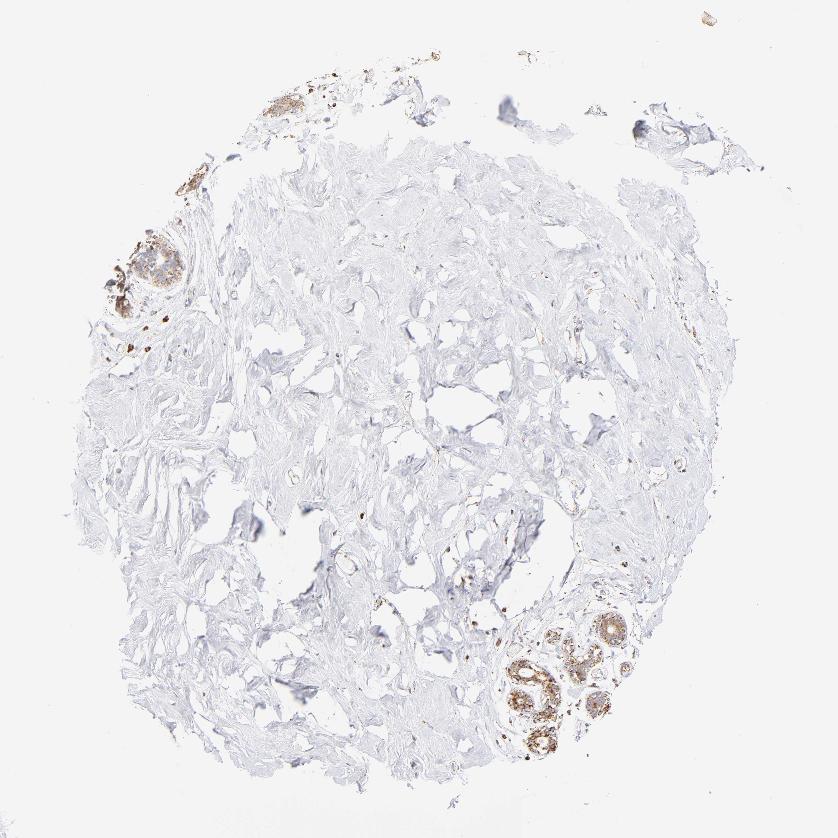

BREAST - Antibody stainingi

Antibody staining in the annotated cell types in the current human tissue is reported as not detected, low, medium, or high, based on conventional immunohistochemistry profiling in selected tissues. This score is based on the combination of the staining intensity and fraction of stained cells.

Each image is clickable and will lead to virtual microscopy that enables deeper exploration of all samples and also displays staining intensity scores, fraction scores and subcellular localization as well as patient and tissue information for each sample.

Antibody HPA002907Antibody HPA005835

Adipocytes -Low

Glandular cells MediumMedium

Myoepithelial cells MediumLow